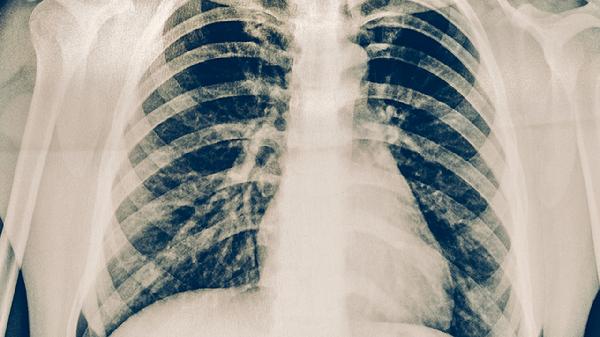

肺结核治疗需坚持6-8个月规范用药,期间出现副作用应及时与主治医生沟通调整方案。保持高蛋白饮食如鸡蛋、鱼肉有助于修复组织损伤,适当补充复合维生素可改善药物导致的营养素消耗。避免与酒精、油腻食物同服减少肝脏负担,治疗期间每1-2个月需复查胸片评估疗效。若出现严重过敏或黄疸应立即停药并急诊处理。